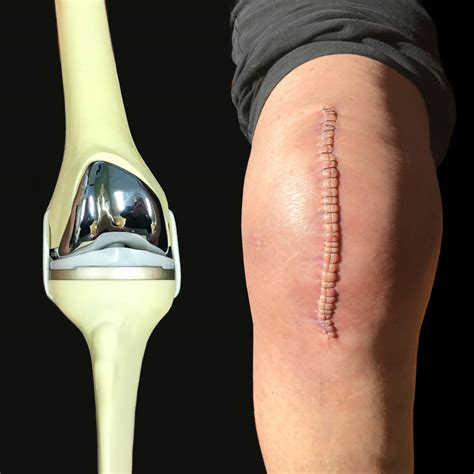

• Incision: The surgeon makes an incision in the knee to access the joint.

• Bone Preparation: The damaged bone and cartilage are removed, and the bone surfaces are prepared to receive the implants.

• Implant Placement: The artificial components are placed and secured with cement or other fixation methods.

• Closure: The incision is closed with sutures or staples, and a dressing is applied.

Here is an example of knee replacement images that illustrate the surgical procedure:

Knee Replacement Procedure

📸 Note: The images above are for illustrative purposes only. Always consult with a healthcare provider for personalized information.